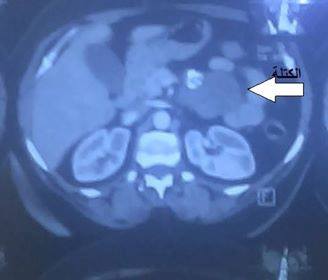

تسليخ كتلة عن البنكرياس و الوريد الكلوي الأيسر واستئصالها بشكل تام من بطن مريضة في (55) سنة من العمر، في مستشفى الامام زين العابدين عليه السلام التابع للعتبة الحسينية المقدسة. وبين قسم العلاقات وإلاعلام في مستشفى الإمام زين العابدين عليه السلام لوكالة نون الخبرية إن الجراحان الدكتور أيمن مرتضى والدكتور إدوارد مهنا اجريا عملية، تم فيها فتح بطن مريضة في (55) سنة من العمر، لرفع ورم نادر (أورام اللحمة المعدية المعوية) (GISTs) gastro intestinal stromal tumor وازالته بعد تسليخه عن جدار البنكرياس و الوريد الكلوي الأيسر واستئصاله بشكل تام و إرساله للدراسة الخلوية، وان المريضة خرجت من المستشفى بحالة عامة جيدة بعد يومين من إجراء العمل الجراحي. فيما أوضح الأطباء المختصين إن هذه الأورام قد تتسرطن أو تبقى سليمة، وتعطي أعراض لا نوعية و يمكن أن تختلط بانثقاب أو نزف أو انسداد يتم التشخيص بالتصوير الطبقي المحوري و الخزعة بالتنظير الموجه بالإيكو أما العلاج فيكون حسب معايير خاصة بالورم تتمثل بالجراحة و المعالجة الهدفية و المعالجة الداعمة و التلطيفية. محسن الحلو وكالة نون الخبرية/خاص